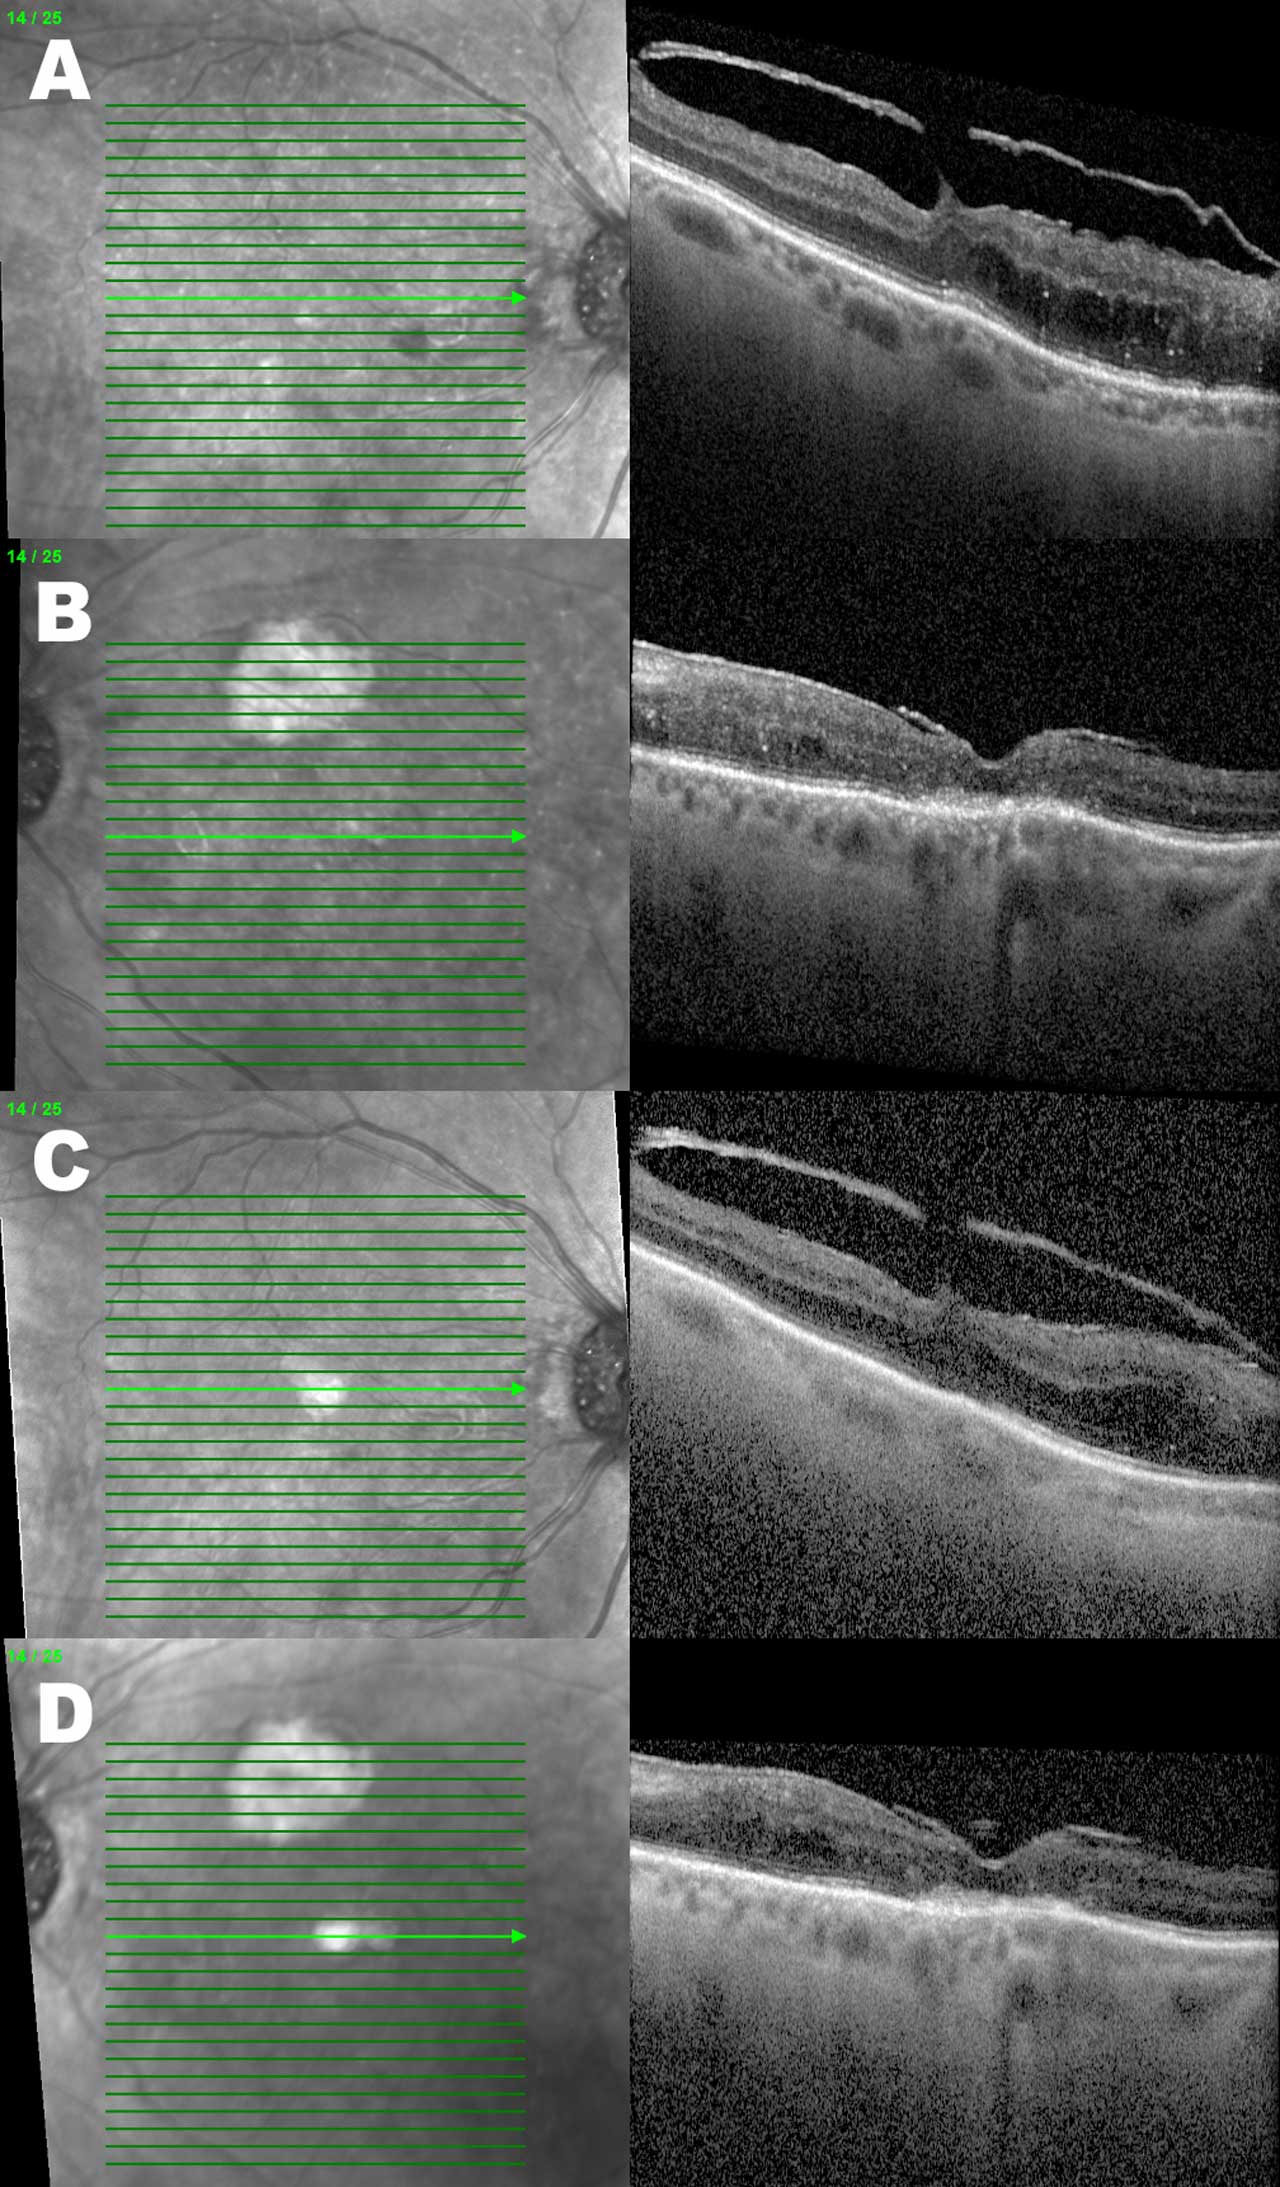

Figures 2 and 3 demonstrate the OCTs of the same patient example who received serial intravitreal injections over 5 months. Besides an overall reduction in the DME-associated retinal thickness, the right eye has a reduction in the quantity of hyperreflective foci present.